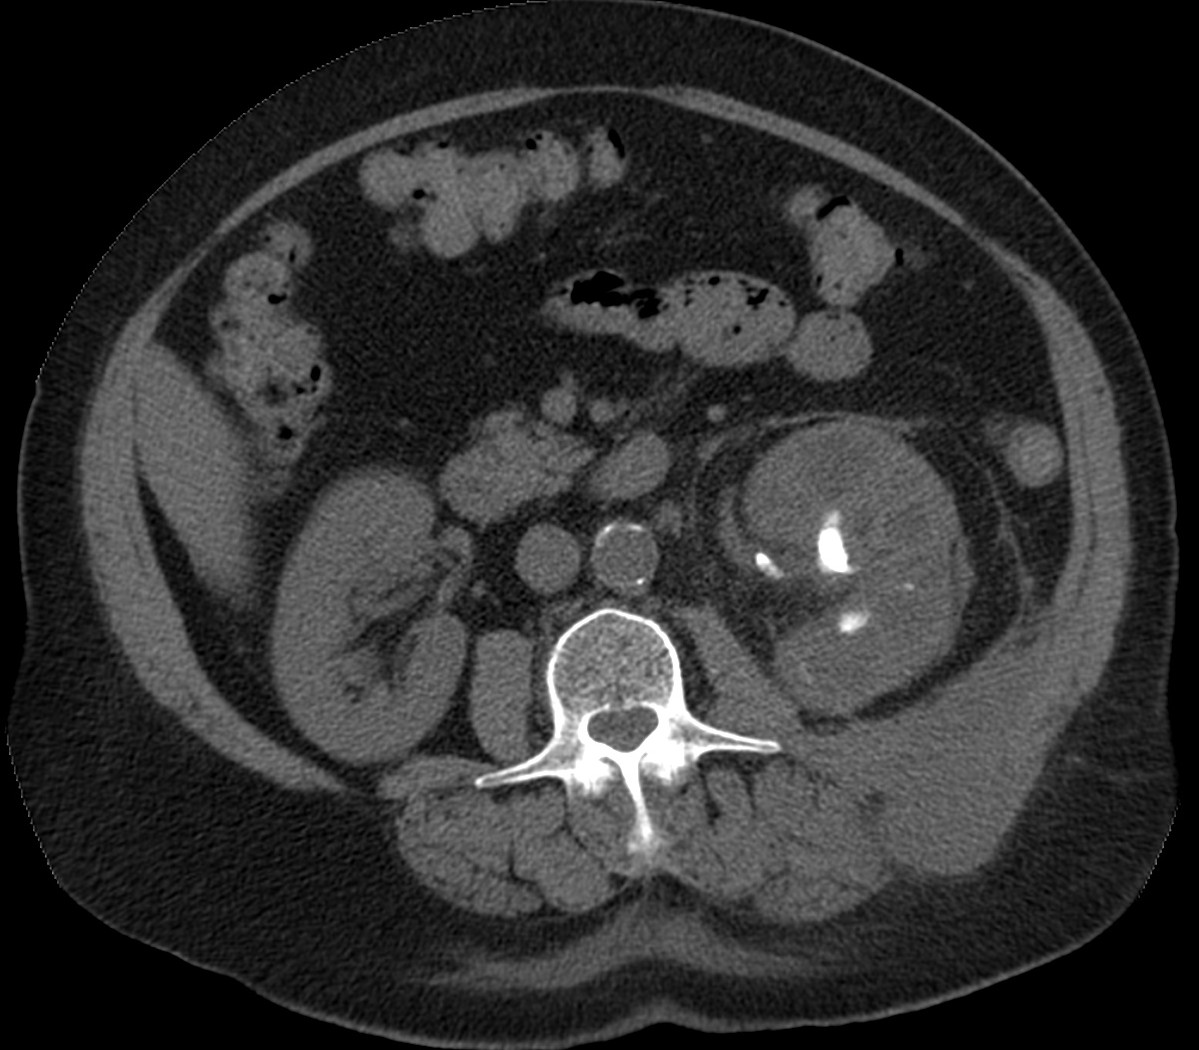

CASO 1: Paciente de 58 años que se realiza TC de abdomen tras historia de dolor abdominal y hematuria microscópica. Refiere pérdida de peso en las últimas semanas.

Estamos ante una afectación bilateral del espacio perirrenal, más evidente en el lado derecho, por masas de densidad de partes blandas en un paciente con numerosas adenopatías retroperitoneales. Estaría indicado realizar una biopsia, ya que el diagnóstico principal orienta hacia un síndrome linfoproliferativo, espcialmente linfoma no Hodgkin tipo B.

2. LINFOMA.

El linfoma renal presenta una gran variedad de manifestaciones. Entre un 3 y un 8 % de linfomas estudiados por TAC tienen afectación renal o perirrenal, más frecuentemente el tipo no Hodgkin.

Patrones de afectación del linfoma renal:

- Multiples masas renales en el riñón (+frecuente)

- Lesión solitaria.

- Adenopatías retroperitoneales con extensión directa a riñón y EPR (nuestro caso de hoy).

- Afectación del espacio perirrenal aislada.

- Infiltración difusa de uno o ambos riñones.

En el caso de que el linfoma afecte al EPR, se ve como una masa homogénea que ocupa este espacio y que desplaza el riñón hacia adelante, ocupando a menudo también el espacio pararrenal anterior. La afectación aislada del EPR por el linfoma es poco frecuente (<10%), es más común la extensión directa desde las adenopatías o grandes conglomerados/masas retroperitoneales (+frec) o la extensión desde el riñón.